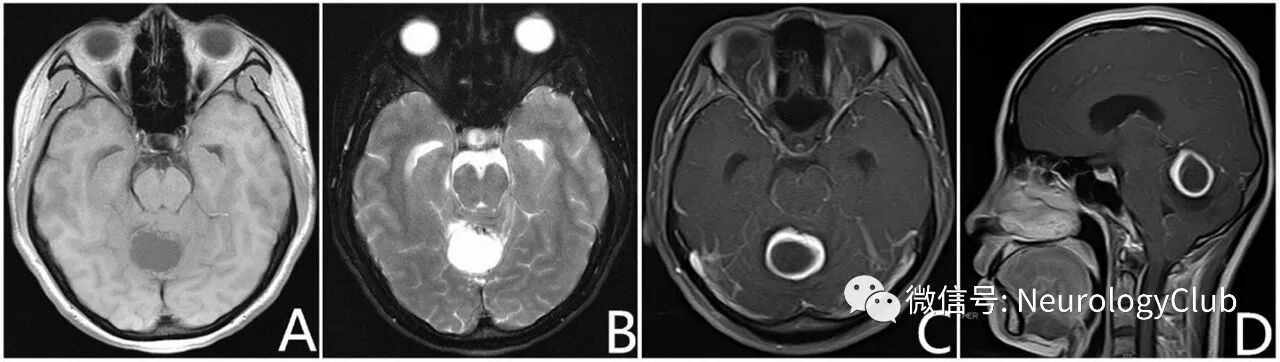

28岁女性患者,表现为头痛,眩晕和耳鸣8月。MRI可见右侧小脑半球囊性肿块(图1A-B)。注射对比剂后病灶呈环形强化不伴有明显的周围水肿(图1C-D)。

(图1:术前头颅MRI可见小脑囊性占位,T1WI呈低信号,T2WI为高信号,增强后可见较规则的环形强化,未见明显周围水肿)